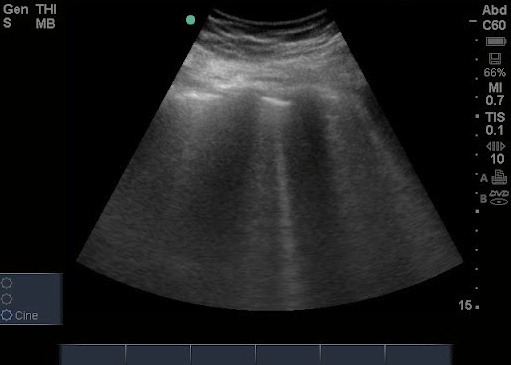

Pacjent leży lub siedzi w wygodnej pozycji. Lekarz nakłada na klatkę piersiową specjalny żel, który ułatwia przewodzenie ultradźwięków, a następnie przesuwa głowicę aparatu wzdłuż żeber i między nimi. Całe badanie trwa zazwyczaj od 10 do 20 minut i jest całkowicie bezbolesne.

W przeciwieństwie do RTG, USG płuc nie wymaga napromieniowania, dlatego może być wykonywane nawet u kobiet w ciąży i dzieci. Wynik dostępny jest od razu po zakończeniu badania.

USG płuc – co wykazuje i co pokazuje?

Ultrasonografia płuc pozwala na wykrycie wielu zmian, których nie zawsze widać na zwykłym zdjęciu rentgenowskim. USG płuc wykazuje m.in.:

- obecność płynu w jamie opłucnej,

- obrzęk płuc,

- zapalenie płuc,

- zrosty opłucnowe,

- zmiany po przebytych infekcjach lub urazach,

- ogniska zapalne lub torbielowate,

- niedodmę i cechy włóknienia.

W sytuacjach nagłych – np. przy duszności, kaszlu czy bólu w klatce piersiowej – USG płuc pokazuje, czy przyczyną objawów może być zapalenie, płyn w opłucnej lub inna patologia wymagająca natychmiastowej interwencji.